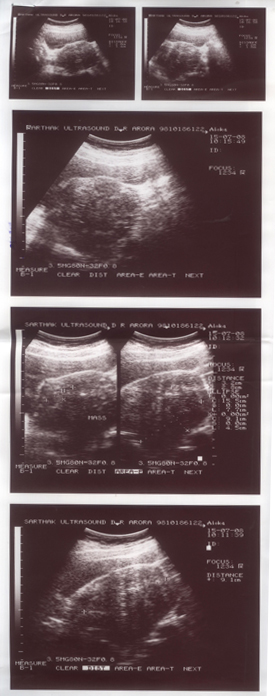

During the treatment:

Her Ultrasound was repeated in November 2008, which showed a decrease in the size of the fibroid, but the endometrial thickness was a matter of concern. With continued treatment latest ultrasound, done in March 2009, showed a marked reduction in the size of the fibroids and also the endometrial thickness came down to 6 mm.